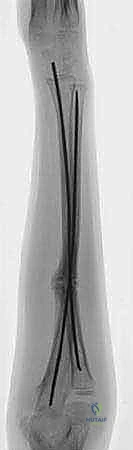

The procedure commences with the establishment of precise entry points, a step that dictates the trajectory of the nails and the ultimate success of the fixation. We typically address the easier fracture first—usually the ulna—to stabilize the forearm segment before tackling the more complex radial reduction. For the ulna, a small 1-2 cm longitudinal incision is made over the lateral aspect of the proximal ulna, approximately 1-2 cm distal to the olecranon apophysis. Blunt dissection is utilized down to the periosteum to avoid injury to the ulnar nerve, which lies medially.

An awl or a drill bit (slightly larger than the selected nail diameter) is used to breach the near cortex. The entry angle is critical; it must begin perpendicular to the bone to prevent skiving, then gradually angle to approximately 45 degrees relative to the shaft axis to facilitate smooth nail passage into the medullary canal.

For the radius, the entry point is established distally. A similar 1-2 cm incision is made over the lateral aspect of the distal radius, proximal to the distal radial physis. Extreme caution must be exercised here to identify and protect the superficial branch of the radial nerve (SRN), which courses directly through this operative field.

The awl is introduced just proximal to the physis, again starting perpendicular and angling proximally.

Prior to insertion, the titanium nails must be meticulously contoured. The radial nail is pre-bent to recreate the normal anatomical radial bow. The apex of the bend should correspond to the location of the fracture to maximize the three-point fixation biomechanics. The ulnar nail is left relatively straight or given a very mild curve to match the native ulnar anatomy.

With the entry portals established, the ulnar nail is introduced first. The nail is mounted on a T-handle and advanced manually with oscillating, twisting motions. Hammering should be avoided if possible, as it increases the risk of cortical perforation or iatrogenic fracture.

The nail is advanced to the level of the fracture site. At this juncture, closed reduction is performed. Traction, counter-traction, and precise manipulation based on the deforming muscular forces (as discussed in the anatomy section) are utilized to align the fragments.

Fluoroscopy is essential here. Once the fracture is aligned, the nail is carefully advanced across the fracture site and seated into the distal ulnar metaphysis.

Attention then turns to the radius. The contoured radial nail is inserted distally and advanced to the fracture.

The radial reduction is often more challenging due to the rotational forces. The surgeon must ensure the radial bow is perfectly restored.

The nail is passed across the fracture site under live fluoroscopy.

The tip of the radial nail should be driven into the proximal radial metaphysis, ideally stopping just short of the proximal physis to avoid growth arrest.

Throughout this process, the surgeon must continuously verify fracture alignment, nail trajectory, and the restoration of the interosseous space on both AP and lateral fluoroscopic views.